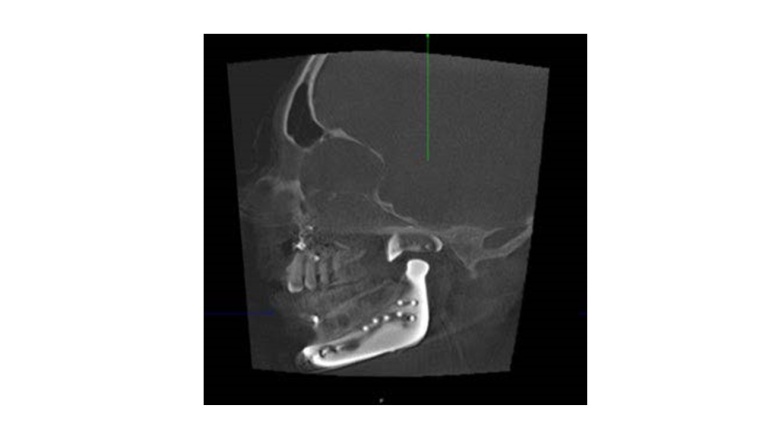

Anhand einer virtuellen Planung und Computerassistierten Behandlung werden bei einer jungen Erwachsenen mit Goldenhar-Symptomenkomplex die Elemente von moderner computerassistierter Planung mit virtueller Blaupausenerstellung für das Operationsergebnis in Verbindung mit der digitalen Dysgnathieplanung als Planungsgrundlage für eine Wiederherstellungsoperation bei angeborener Gesichtsschädeldeformität dargestellt; verknüpft wird dieses Rekonstruktionsbeispiel zudem mit erweiterten Total Joint Replacement, das digital geplant und gefertigt wurde.

Aus der jetzigen Konturbetrachtung der Hartgewebestrukturen von Corpus mandibulae, Kinnprojektion, Kieferwinkel und Anteilen des aufsteigenden Astes kann ggf. die Notwendigkeit eines Ersatzes, der betroffenen Kiefergelenkregion durch ein Total Joint Replacement notwendig werden. Es bedarf einer Gelenkpfannen-Komponente, die im Hinblick auf die deformierte Schädelbasissituation individuell angepasst sein muss und ggf. auch fehlende Jochbogenanteile – wie in diesem Fall - simultan mit ersetzt. Für die spätere Verankerung sind sowohl die chirurgisch vorbereitenden Maßnahmen zur Schädelbasis und auch die Bohrvorgänge und Schraubeninsertionen zu Verankerungen der Pfannen-Komponente durch Real-Time-Navigation unbedingt zu unterstützen. So lassen sich bei den deformierten Weich- und Hartgewebesituationen sicher die knöchernen Verankerungsmöglichkeiten nachvollziehen und chirurgisch umsetzen, und auch wichtige anatomische Strukturen, wie z. B. die großen Gefäße an der Schädelbasis, können geschont werden. Das skelettale Delta zur Schädelbasis im Bereich des aufsteigenden Astes, im Bereich des Kieferwinkels und des betroffenen Unterkieferkörpers mit insbesondere der Projektion nach unten und seitlich bis einschließlich zur Kinnregion, lässt sich nunmehr in das Design des Implantates für den patientenspezifischen Gelenkersatz integrieren. Hier wird durch biomedizintechnische Innovationen aufgrund von Computer-Assistenz und modernsten digitalen Planungs- und Fertigungstechniken deutlich, wie sich für die Patienten mit schweren angeborenen Fehlbildungen aus einer sonst langdauernden und viele Operationen umfassenden Behandlung eine drastische Therapieverbesserung erzielen lässt.